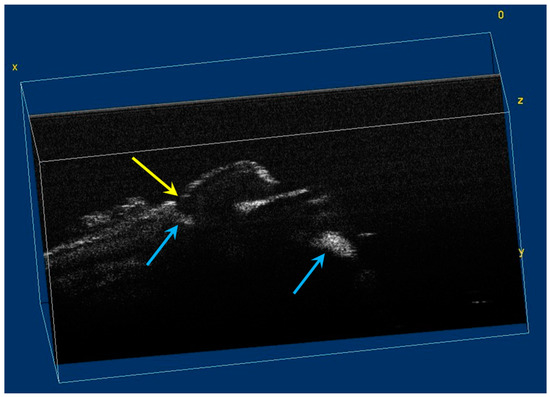

The image processing using ImageJ software showed the spatial disposition and extent of the hypomineralization lesions and hypoplasia (Figure 6, Figure 7, Figure 8 and Figure 9).

Figure 6.

Three-dimensional OCT reconstruction of hypomineralization areas (Axis 0Y). The blue arrows indicate three well-defined areas; the yellow arrows indicate several small-size diffuse areas.